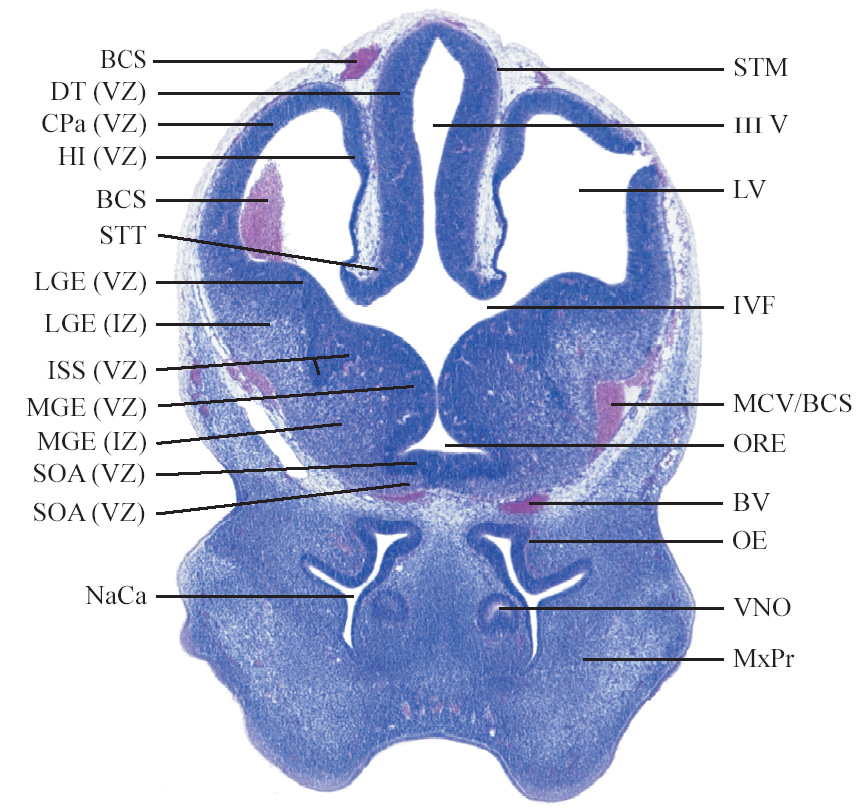

C57BL/6J GD12 Mouse Brain Atlas

Slides from U. Schambra, coronal cuts with slides at every 5th section, with a hematoxylin and eosin (H & E) stain

Currently on section 80.